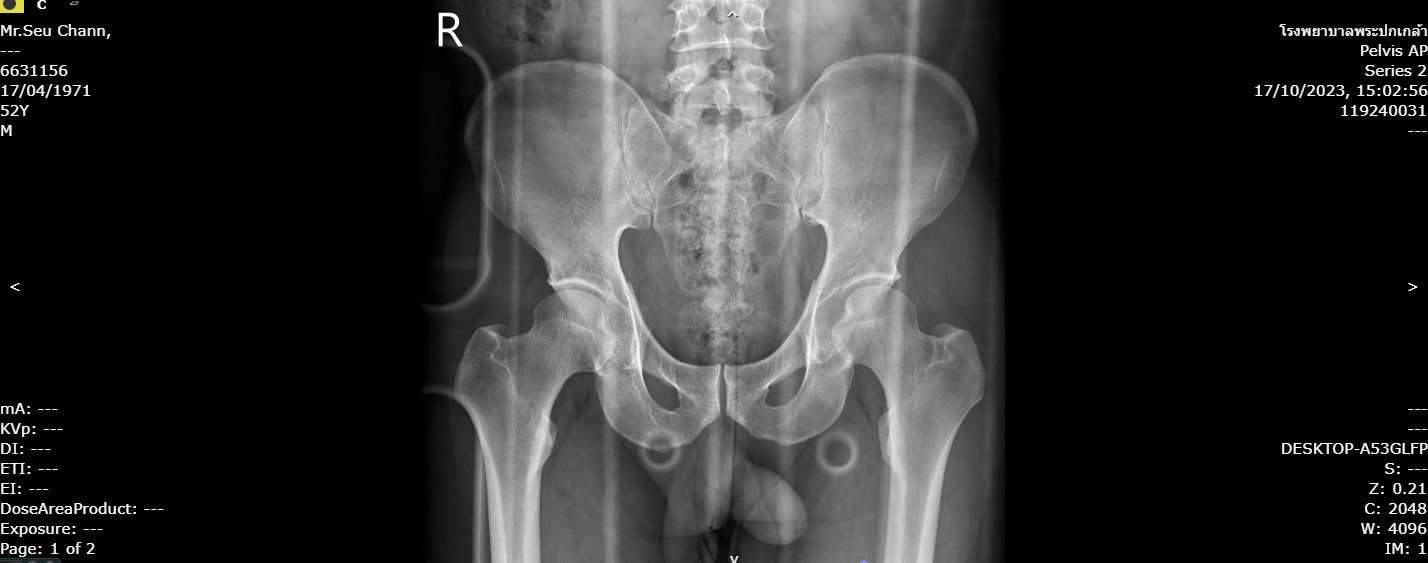

163mr.seu.jpg                                      11-Apr-2024 05:57               97946